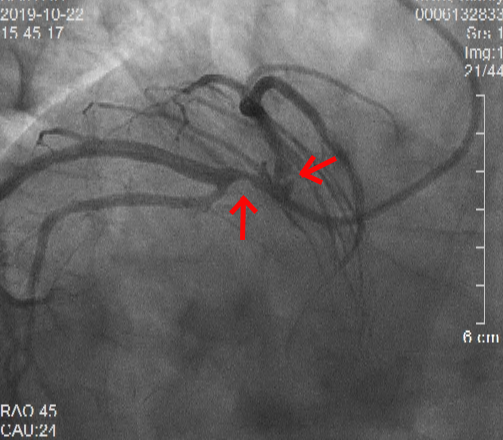

术前冠状动脉造影显示:镜像右位心、前降支和回旋支开口处严重病变